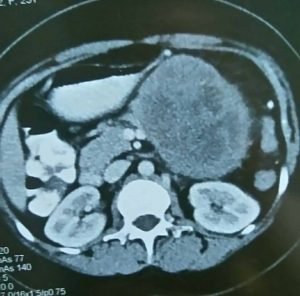

و أيضاً هناك إهتمام منا بنوعية من أورام البنكرياس وهي أورام البنكرياس الكيسية Pancreatic Cystic Neoplasmas وهذه الأورام تكون علي هيئة أكياس في البنكرياس وهناك اهتمام عالمي بها في الآونة الأخيرة نظراً لزيادة معدل إكتشاف هذه الأورام الكيسية وذلك بإستخدام وسائل التشخيص بالأشعة الحديثة مثل الأشعة المقطعية والأشعة بالرنين المغناطيسي والأشعة بالموجات فوق الصوتية بالمنظار مع إمكانية أخذ عينات بواسطة إبرة دقيقة من هذه الأورام لتحليل السائل والخلايا والأنسجة الموجودة في هذه الأورام.

وهناك أنواع مختلفة من هذه الأورام الكيسية فعلي سبيل المثال هناك الاورام الكيسية المصلية Serous Cystic Neoplasmas وهناك الأورام الكيسية المخاطية مثل Mucinous Cystic Neoplasmas وكذلك Intraductal Papillary Mucinous Neoplasmas وهناك الأورام الصماء الكيسية Solid Cystic Pseudopapillary Neoplasmas وهناك أورام أخري لايتسع المجال هنا لذكرها.

وعلاج هذه الأورام يحتاج إلى التشخيص الدقيق وإجراء العملية الجراحية المناسبة حسب نوع وحجم ومكان الورم وحسب نوعية الخلايا الموجودة في الورم سواء كانت حميدة أم خبيثة ودرجتها، وكذلك حسب عمر المريض أو المريضة والحالة الصحية.